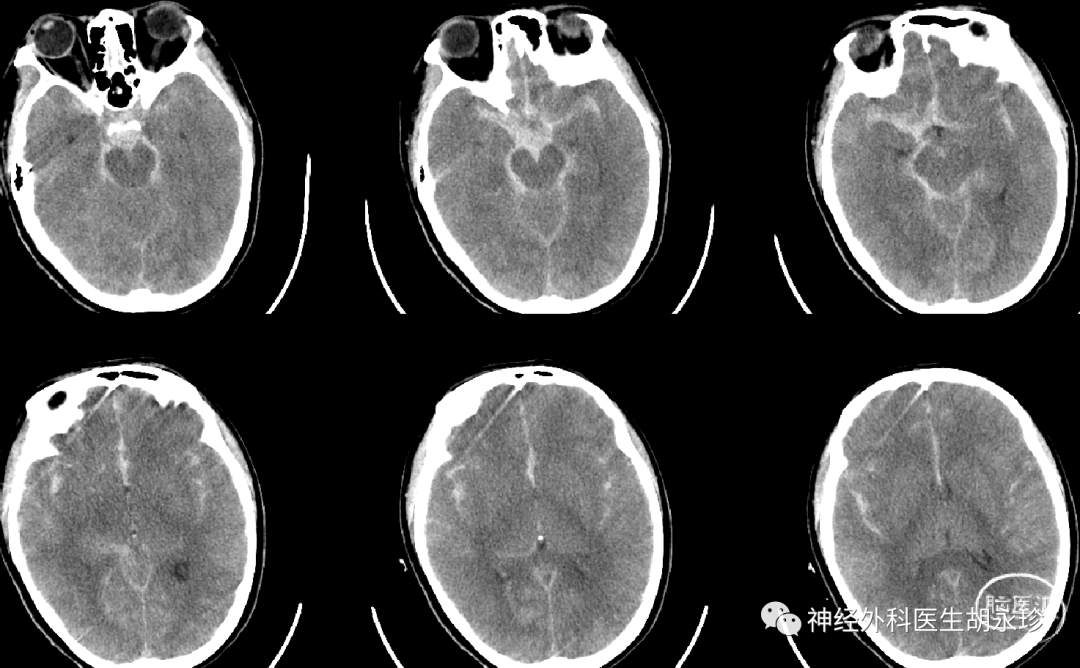

患者血压不稳波动于66/34—116/60mmHg,先后予多巴胺调控血压。心电图示 T 波改变。考虑为神经源性肺水肿,不除外心脏损害。于次日意识转为浅昏迷,双瞳孔不等大,右侧瞳孔直径约 5mm,光反射消失,四肢肌力无法查,肌张力高 。行头颅 CT级CTA(如下图)示:右侧鞍旁血肿破入脑室,右侧后交通动脉瘤,瘤颈宽约 2. 2mm,纵径约5. 8mm。胸部 CT(如下图):双肺较对称团片状渗出高密度影。

结果与颅脑及胸部CT旧片对照:大量蛛网膜下腔出血,较前稍增多。脑肿胀,合并轻度缺血缺氧性脑改变,以上改变较前稍明显。新见右侧颈内动脉结节致密影,结合临床病史考虑右侧颈内动脉瘤术后改变;颅脑HRCT能谱分析显示目前未见明确造影剂外渗征象,考虑神经源性肺水肿,双肺渗出较前明显增多,建议治疗后短期内复查。